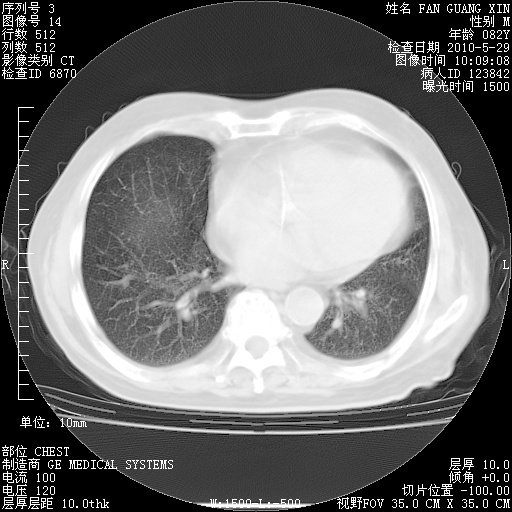

再治疗10天后的肺部CT

从白细胞总数和中性比例看好像合并感染。肺部纹理好像比上次多,支气管炎?其他感染?

阅读此次胸部CT,肺间质渗出性改变较入院时有吸收。目前从体温、白细胞、中性分叶明显增高,肯定存在细菌感染(发生医院感染哦,若无消化道及泌尿系统等感染的依据,肺部感染可能大)。若你院头孢哌酮舒巴坦钠耐药率较高,同意你的方案,若48小时体温仍高,可考虑使用碳青霉稀类抗菌药物,同时可予超声雾化、注意滴数时加大液体量。白蛋白33.30g/L较低哦,需加强营养等支持治疗。